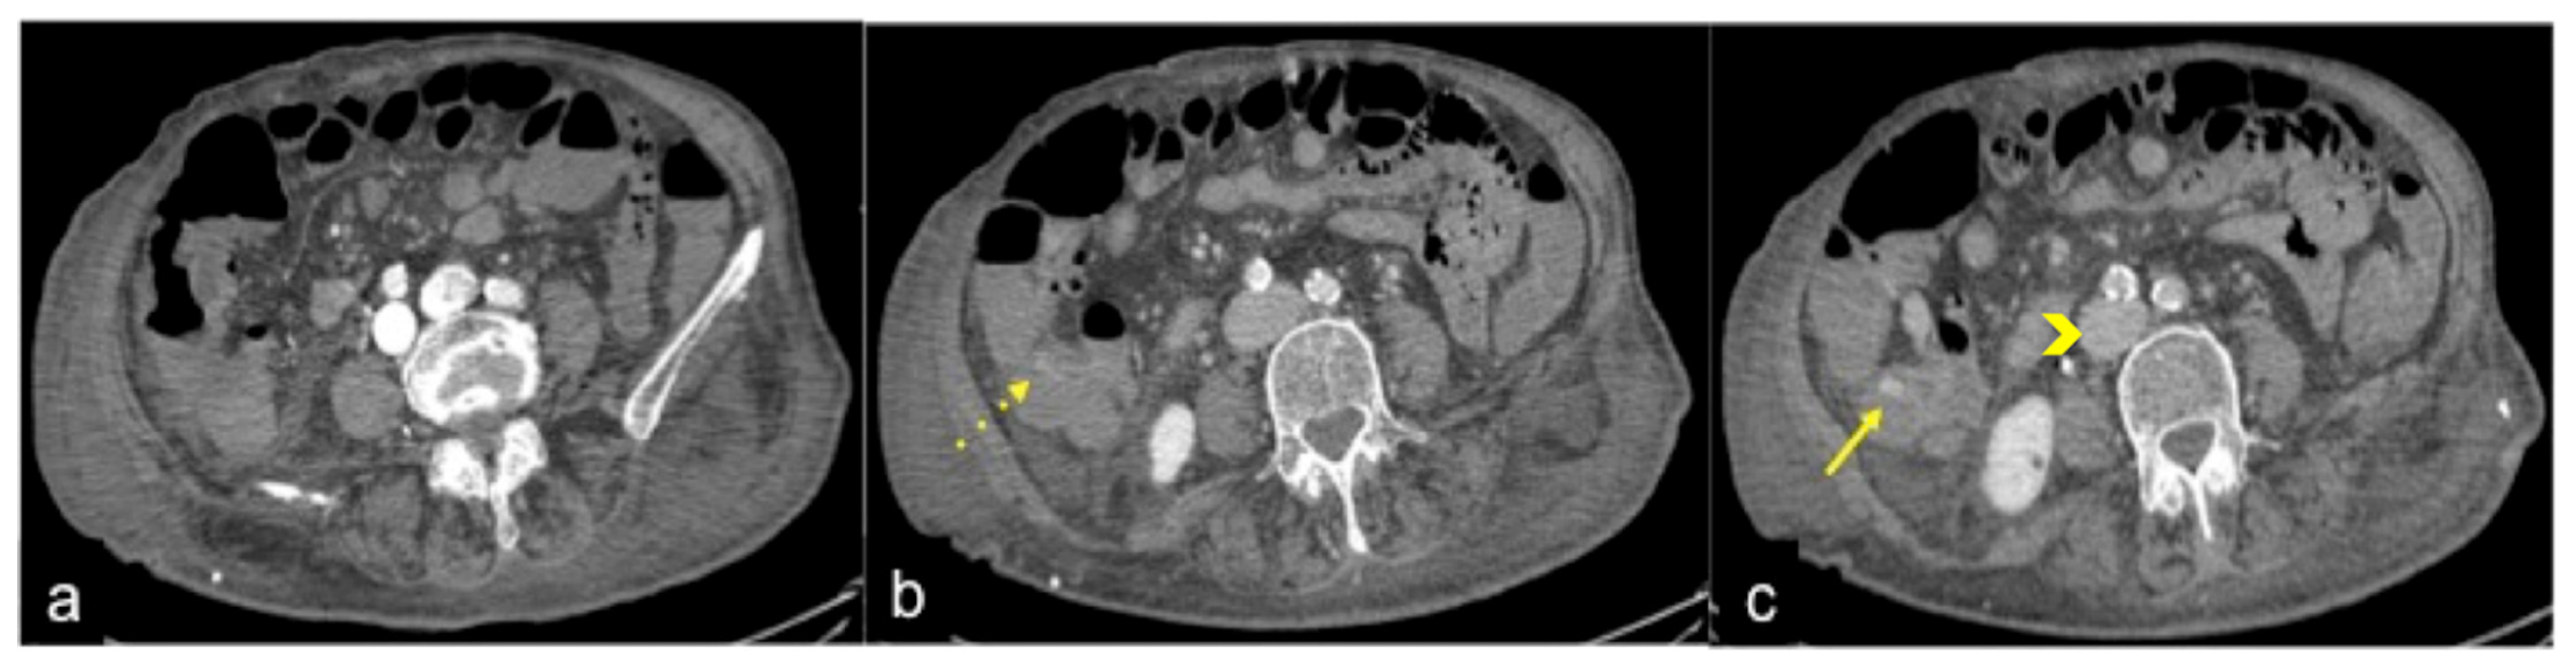

| Aorto-Enteric Fistula (Figure 31) | Bleeding in a patient with a history of surgery for aortic aneurysm. | A connection between the aorta and the intestinal lumen. Absence of adipose cleavage planes. |